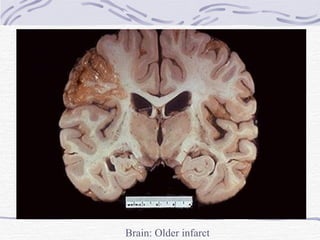

CNS Infarction Infarction contd. 1-2 weeks – Swelling resolves Softening Shrunken granular grey matter Accumulation of lipid-laden phagocytes (gitter cells) in infarcted area Several months – shrunken cystic lesion traversed by glial fibrils and small blood vessels

Brain: Older infarct showing cavity formation

Brain: Older infarct